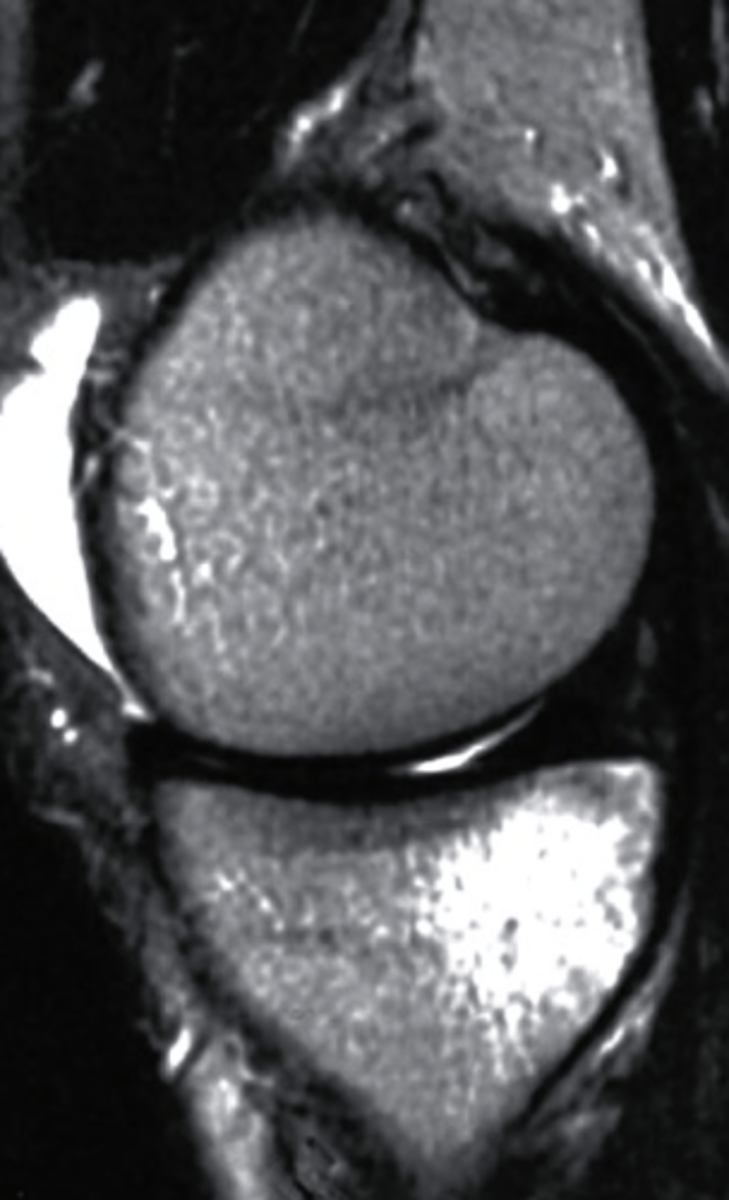

T2 MRI

what type of imaging is this?

a. T2 MRI

b. CT Scan

c. Radiograph

d. T1 MRI

bone marrow edema

what can be seen in this MRI?

a. bone tumor

b. bone marrow edema

c. fracture in the bone

d. bone bruising

what type of image is this?

c. T1 MRI

d. conventional radiograph

bone bruise, T2 MRI

what can be seen on the medial tibial plateau in this image and what type of image is this?

a. tumor, T1 MRI

b. complex fracture, CT scan

c. bone bruise, T2 MRI

d. AVN, conventional radiograph

sagittal

What plane is this MRI?

a. sagittal

b. coronal

c. axial

d. AP